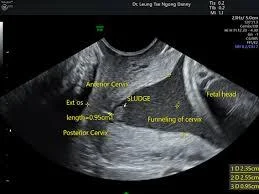

Diagnosis of cervical incompetence: Z

-

From history

- Three or more miscarriage es.

- Painless vaginal bleeding.

- decreased gestational age in subsequent pregnancy.

From investigations:

- Hagar dilator(No.8).

- HSG.

- During pregnancy: US Funnel shape, short cervix.

Management:

- Cervical cerclage.